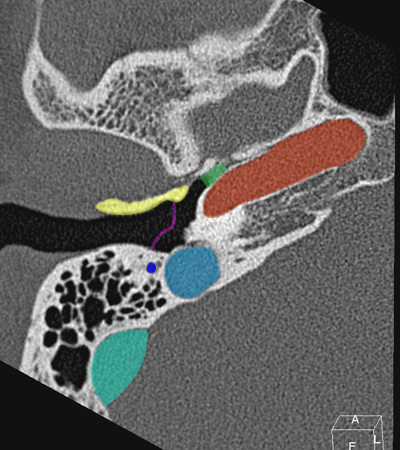

Radioanatomie du rocher sur coupes TDM

Différentes coupes de référence (A. Attyé 2013)

Coupe axiale passant par le canal semi-circulaire supérieur Coupe axiale passant par le canal semi-circulaire latéral Coupe axiale passant par le modiolus de la cochlée Coupe axiale passant par la fenêtre ronde Coupe axiale passant par le ganglion géniculé Coupe axiale passant par l'articulation incudo-malléaire Coupe axiale passant par la partie pétreuse de l'artère carotide interne Coupe axiale passant par le nerf tympanique

Coupe axiale passant par le foramen styloïde Coupe coronale passant par le muscle tenseur du tympan Coupe coronale passant par le recessus epitympanique Coupe sagittale passant par le segment mastoïdien du nerf facial coupe sagitalle oblique passant par le canal semi-circulaire supérieur (plan de Pöschl) Reconstruction axiale passant par le plan de l'étrier Coupe axiale passant par les apex pétreux